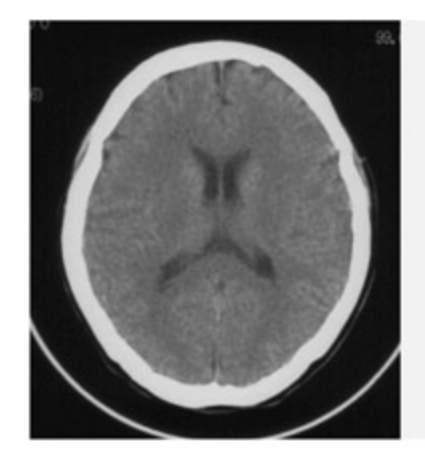

Computerized tomography (CT) scans are constructed according to the amount of X-ray absorption in different types of tissue. e amount of absorption is related to tissue density: bone absorbs the most (and so the skull appears white), cerebrospinal fluid absorbs the least (so the ventricles appear bla), and the brain maer is intermediate (and appears gray). Given that CT uses X-rays, the person being scanned is exposed to a small amount of radiation.

CT scans are typically used only in clinical seings, for example to diagnose tumors or to identify hemorrhaging or other gross brain anomalies. CT cannot distinguish between gray maer and white maer in the same way as MRI, and it cannot be adapted for functional imaging purposes.

📊 그림 설명

컴퓨터 단층 촬영(CT) 뇌 스캔 이미지이다. X선 흡수량에 따라 뼈(두개골)는 흰색, 뇌척수액(뇌실)은 검은색, 뇌 조직은 회색으로 나타난다. CT는 종양이나 출혈 진단에 주로 사용되지만, 회백질과 백질을 구분하지 못하는 한계가 있다.

An example of CT (le), T1-weighted MRI (center), and T2-weighted MRI (right) scans of the brain. Note how the MRI scans are able to distinguish between gray maer and white maer. On the T1 weighted scan (normally used for structural images), gray maer appears gray and white maer appears lighter.